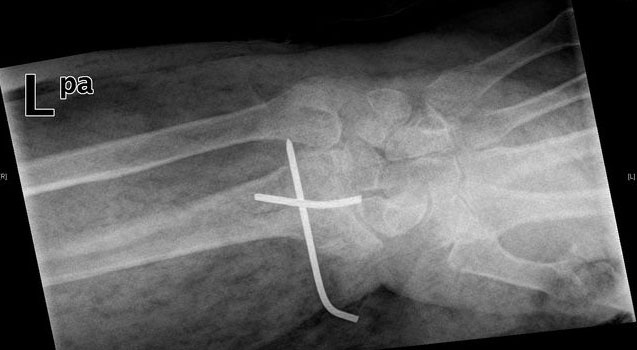

Tratamiento de fractura de radio con agujas.

Tratamiento con agujas de fractura de radio.